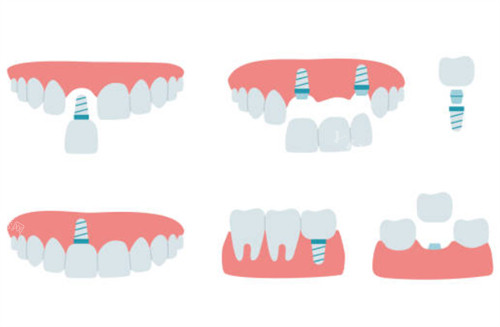

在儿童齿科、种植牙、洗牙等核心项目上实力突出,配备儿童专用口腔 CT、智能化种植导航系统等靠前设备,医生团队平均从业经验 8 年以上,尤其擅长儿童龋齿防治、成人复杂种植牙等诊疗项目,多年来帮助众多患者解决口腔问题,积累了大量好评。